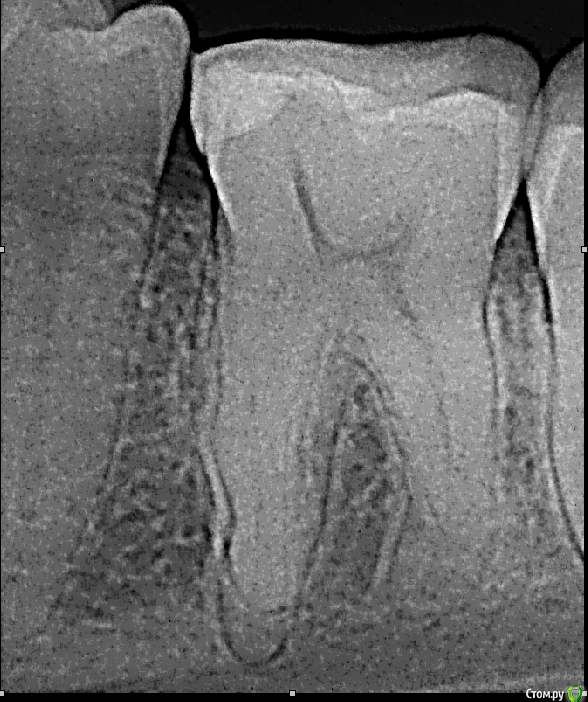

vse32 Опубликовано 22 мая, 2016 Поделиться Опубликовано 22 мая, 2016 устья что то на rg не увидел, и в канал бы не попал, не видя куда. Вот только куда бурить дальше если он на уровне бифуркации , страшно рассверлить псевдо ход ,без увеличения , без визуального контроля ? Про ходы, на сколько градусов можно отклонение ? Можно по подробнее ? У меня возникает следующая проблемма: верхняя челюсть, моляры,поиск дистально-щечного , когда кудельцы провели пульпотомию закрыли сицем , и все кирдык , опускаюсь ниже коронковой части и где должно быть устье иже ход канала продолжается цемент, убить готов, ей Богу . Хотя если остановится, и до завтра, пациенты отмечают снижение боли, но не ее отсутствие. После пары загубленных зубов при такой картине вообще останавливаюсь и отправляю на микроскоп или искать более опытных. После таких провалов страшно вообще что либо переплачивать. А условия острая боль и отсутствие rg в отделении и такой сюрприз в зубе доводит до белого каления и без того разкочегаренное место. МБ обезболить и отсылать на rg? Гуру госок отзавись =)) http://www.edentworld.ru/u6.jpghttp://s020.radikal.ru/i709/1605/0e/d7c330b0ead6.jpghttp://s019.radikal.ru/i619/1605/86/2bd730811cd7.jpgЭто левый верхний первый моляр.Что-бы зайти в МД - инструмент вводим от середины - медиальной стенки или чуть более небно, острота угла вариабельна.А что-бы зайти в МБ1 - инструмент, фактически нужно положить из области дистального небного бугра, острота угла вариабельна.Я не претендую на звание гуру Госа, но 15 лет я там отбарабанила.1 год в интернатуре - без рентгена, без наставника, без приличных материалов и инстументов. Контингент - Ветераны труда со склерозированными каналами. После этого могла лечить периодонтиты "силой мысли", и выходить с голыми руками на медведя. )))Потом еще 14 лет в более благоустроенной поликлинике. Там, считай все супер было. Рентген был 4 часа в смену (смена 6 часов). Если, конечно рентгенолог не болел, не учился или в отпуске не был. А у них эти периоды часто и надолго. Только хождение пациента от меня до рентгенолога и обратно занимало от 10 до 50 минут. Диагностика периодонтита и контроль пломбировки еще туда-сюда, а вот сделать серию снимков во время ретрита - утопия. Тут то и развивается чутье в пятой точке. ))))Если что рядом была частная клиника, куда можно было в случае отсутствия снимков направить пациентов. Минус, снимки приходили на А4 на обычной бумаге.Материальное обеспечение вполне неплохое. Что не давали, докупали сами, так как начальство в то время лояльно относилось к подработкам врачей.Отсюда вопрос. Я вижу в профиле местоположение Сибирь. Я думаю в Сибири есть достаточно крупные города, а есть сильно помельче. В каком городе работаете Вы? В Москве, на данный момент, устроится в простенькую клинику, но с рентгеном и кальцием - не самая большая проблема. Зарплата, по любому, будет выше чем в сейчас в Госе.Второе, что Вас держит в таком убогом Госе? Возможность набить руку? - так Вы своих результатов не видите. Возможность подработать - тогда покупка кальция за 200 рублей не проблема. Возраст - так в коммерции давно к этому проще стали относиться. Самой убедительной причиной для меня будет отсутствие другого места работы, как такового.Я почему стала рассуждать на тему вашего места работы. Сама не так давно в коммерции. Сейчас частенько думаю, на кой черт я столько времени сидела в Госе? Что меня там держало? Думаю - страх что-то менять. А вот борьба с ветряными мельницами сильно доставала. Попробуйте порассуждать на эту тему.Вы не представляете как это прекрасно, когда время на пациента Вы задаете сами, когда есть время все задуманное сделать за раз. Когда в дверь не вваливается очередная неожиданная острая боль. Когда пациенты спокойно лечатся, а не занимаются качанием прав и "Вы мне тут все должны, я жалобу напишу и проч." Когда рентген всегда под рукой и по много раз. А по поводу каналов, направление, углы - это половина успеха, точно Вам говорю. Если есть УЗ - было бы здорово сначала разработать устья насадкой с тонки кончиком. Такие насадки обычно нужны для снятия камней в межзубных пространствах. Но и каналы иногда на 1/4 проходят за раз. Главное не давить, а тихонечко прощупать дно и найти самую слабую точку. Скорее всего она и окажется устьем.Никогда не расширяйте устья еще непройденных каналов Ларго или Пизо римером. 99% нарежете ступеней и потом вообще никуда не пройдете. Максимум - легонько твердосплавным шариком на механике. И то редко требуется. Очень надеюсь, что под рукой есть апекслокатор. Отсутствие аплока и Rg делают эндодонтию почти бессмысленным занятием. Это уже полевая стоматология, и никак не больше. 5 Ссылка на комментарий